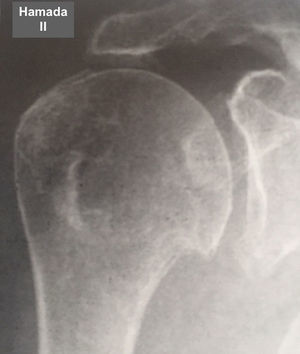

Fue elaborada por Hamada (tabla 6 y figs. 7–11) para describir el tipo de artropatía en roturas masivas del manguito de los rotadores. Utiliza la radiografía convencional y las características de la articulación glenohumeral y el ascenso de la cabeza del húmero para determinar el grado de la lesión. Muestra una correlación quirúrgica y radiológica de cerca del 80%10.